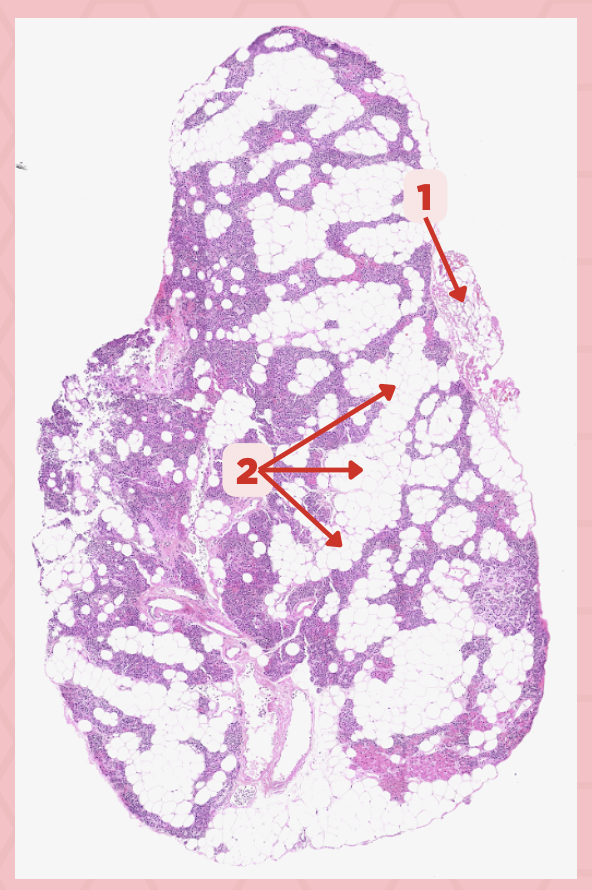

The parathyroid gland is divided into _____, packed with epithelial cells that form cords and clusters.

False

TRUE or FALSE. The parathyroid gland is only enveloped by its own thin connective tissue capsule.

Parathyroid Capsule

Identify the structure labeled as 1.

Lobules

Identify the structure labeled as 2.

Septa

Identify the structure labeled as 3.

Parathyroid

Identify the specimen.

Parathyroid

Identify the specimen.

Parathyroid

Identify the specimen.